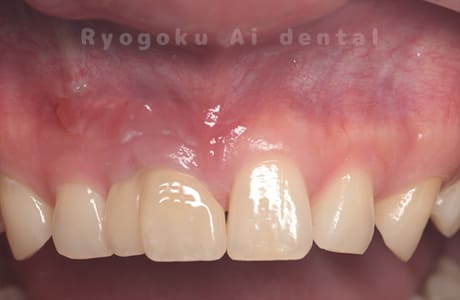

前歯の腫れが治らない、とのことでご来院された患者様です。前歯には他院で自費で入れた被せ物が入っており、被せ物のやり変えと共に根管治療の提案を致しましたが、このままの状態での治療を希望されたため、歯根端切除術を行いました。手術後の痕も気にならずに、腫れもなくなり、非常に満足して頂きました。半年経過を追っておりますが、現在も再発等ございません。

<リスク・副作用>

外科手術のため、術後に出血、痛みや腫れ、違和感を伴います。口腔内の状態によっては適応できないことがあります。歯根端切除で治らなければ抜歯を検討しなくていけない場合もあります。